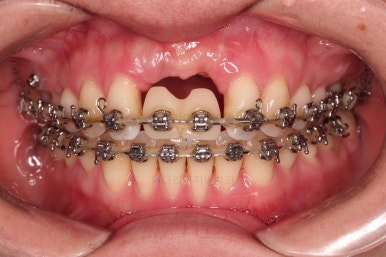

1. 초진

부산개방교합 키다리아저씨치과에 처음 내원 시 입안의 모습입니다.

전반적으로 치열이 삐뚤고요.

앞니쪽이 다물어지지 않는 개방교합(오픈바이트, open bite) 을 보였습니다.

어금니 맞물림을 보면 앵글씨 2급 부정교합 양상이어서 위아랫니가 모두 1대1로 부딪히고 있는 상태였습니다.